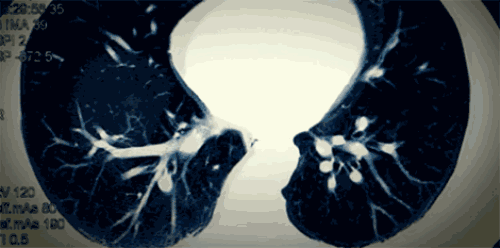

你会发现,它的致死剂量确实很低,这是因为百草枯不像其它有毒物质那样,在人体中会被慢慢中和和排出,百草枯毒性有点像催化剂的效果,它被肺吸收后,在肺部慢慢纤维化的过程中,百草枯的量并没有减少,所以肺部会持续纤维化下去。

图注:百草枯误食纤维化的肺

肺部的纤维化是不可逆的,加上它是被快速吸收和渗透,医治确实是一个难题。